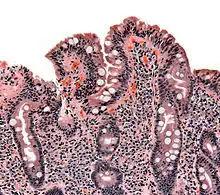

| The ileocecal valve prevents reflux of bacteria from the colon into the small bowel. Resection of the valve can lead to bacterial overgrowth. | |

The diagnosis of bacterial overgrowth is made by a number of techniques, with the gold standard[3] being an aspirate from the jejunum that grows in excess of 105 bacteria per millilitre. Risk factors for the development of bacterial overgrowth include dysmotility; anatomical disturbances in the bowel, including fistulae, diverticula and blind loops created after surgery, and resection of the ileo-cecal valve; gastroenteritis-induced alterations to the small intestine; and the use of certain medications, including proton pump inhibitors.

Finally, abnormal connections between the bacteria-rich colon and the small bowel can increase the bacterial load in the small bowel. Patients with Crohn's disease or other diseases of the ileum may require surgery that removes the ileocecal valve connecting the small and large bowel; this leads to an increased reflux of bacteria into the small bowel. After bariatric surgery for obesity, connections between the stomach and the ileum can be formed, which may increase bacterial load in the small bowel.[26]